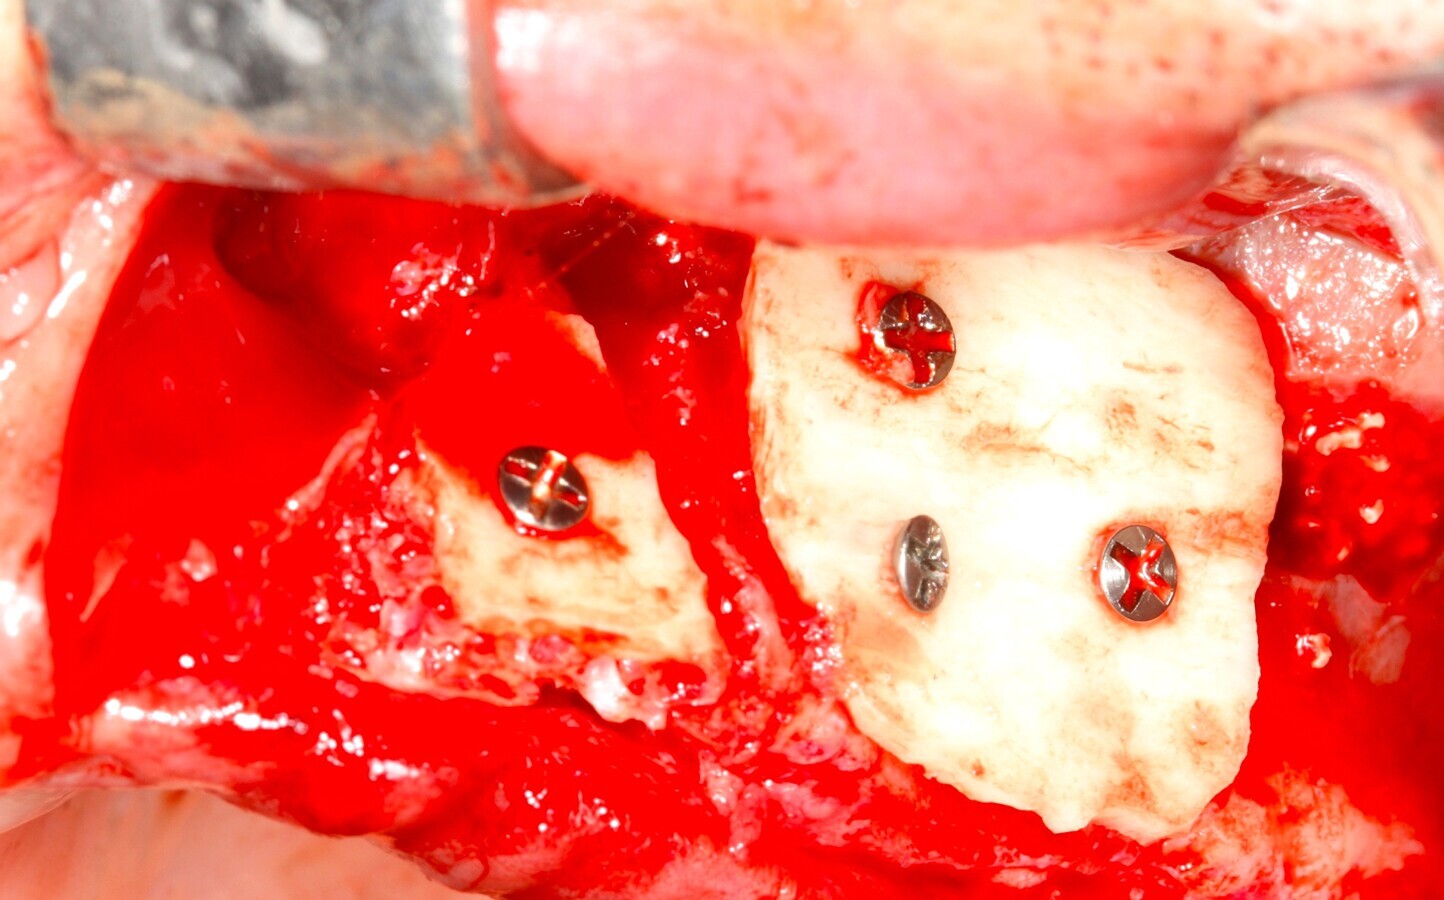

Fig. 15 Figura 15

5. Fijación del injerto previamente modelado al lecho con microtornillo de 1.5 a 2 mm de diámetro.

Fig. 16 Figura 16

6. Relleno de hueso particulado en la intersección entre el injerto óseo y el lecho receptor.